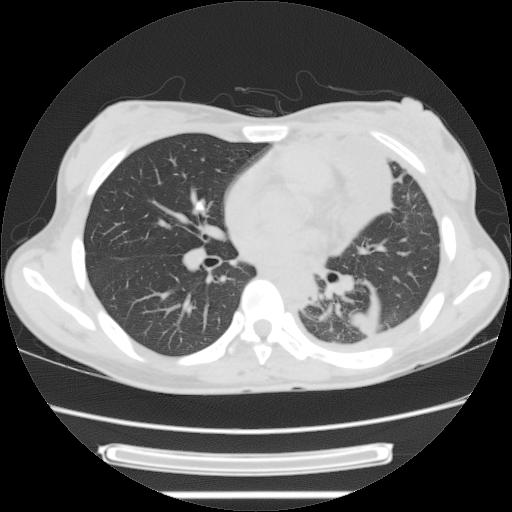

女,29岁,胸部不适,在外院胸片提示胸腔积液,到我院ct检查。

肺窗:

1、左侧包裹性积液伴叶间积液 2、右肺多发结节考虑增殖结节

左肺上叶不张,左侧胸水,叶间裂积液,纵隔淋巴结,脾脏钙化,考虑左肺上叶支气管内膜结核,结核性胸膜炎,脾结核

考虑两肺结核,左侧包裹性积液,叶间积液。

右肺多发结节。左胸腔多发包裹性积液。

左肺上叶不张,左侧胸水,叶间裂积液,纵隔淋巴结,脾脏钙化,考虑左肺上叶支气管内膜结核,结核性胸膜炎,脾结核。支持!